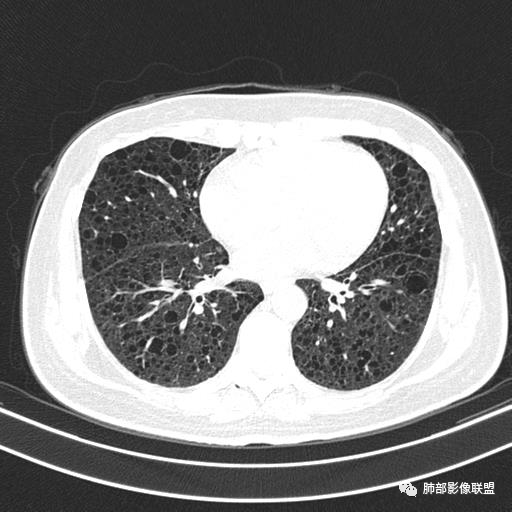

双肺弥漫囊腔,累及肋膈角,囊腔形态相对规则单一。

CT平扫示双肺弥漫分布大小不等囊状薄壁透光区,无内、中、外带分布差异,间质稍示增厚。拟LAM

中年女性育龄期妇女,咳嗽气喘,无吸烟史,有苯吸入史。影像:双肺弥漫均匀小囊腔,无明显分布优势,囊腔形态欠规则,壁薄,部分囊腔边缘血管征,伴双肺弥漫磨玻璃影,无结节,考虑lam,鉴别苯中毒肺损伤,囊腔多有分布优势,小叶中心分布为主,形态规整等

女,46,活动性气喘1年。苯吸入史半年。胸部CT:两肺弥漫囊腔,上至肺尖,下至肋膈角,形态类似小囊腔。考虑:LAM,鉴别LIP,BHD,PLCH等。

双肺弥漫大小不一薄壁含气囊腔,囊间肺组织正常,正常肺背景,肺尖肺底受累;青年女性,气喘,支持LAM

双肺多发大小相近的囊状影,分布趋势趋于一致,中年女性,考虑LAM。部分囊内见血管及分隔影,小叶中心性肺气肿代排

CT表现:双肺弥漫大小不等的薄壁囊腔,囊壁<2mm,外形规则,血管影多位于囊腔周围,囊腔之间肺组织正常,随着疾病进展到晚期,囊腔变大、增多,不可胜数,囊腔可融合成较大的囊,与肺气肿相似,形成间质性肺纤维化。部分病例可出现结节影。